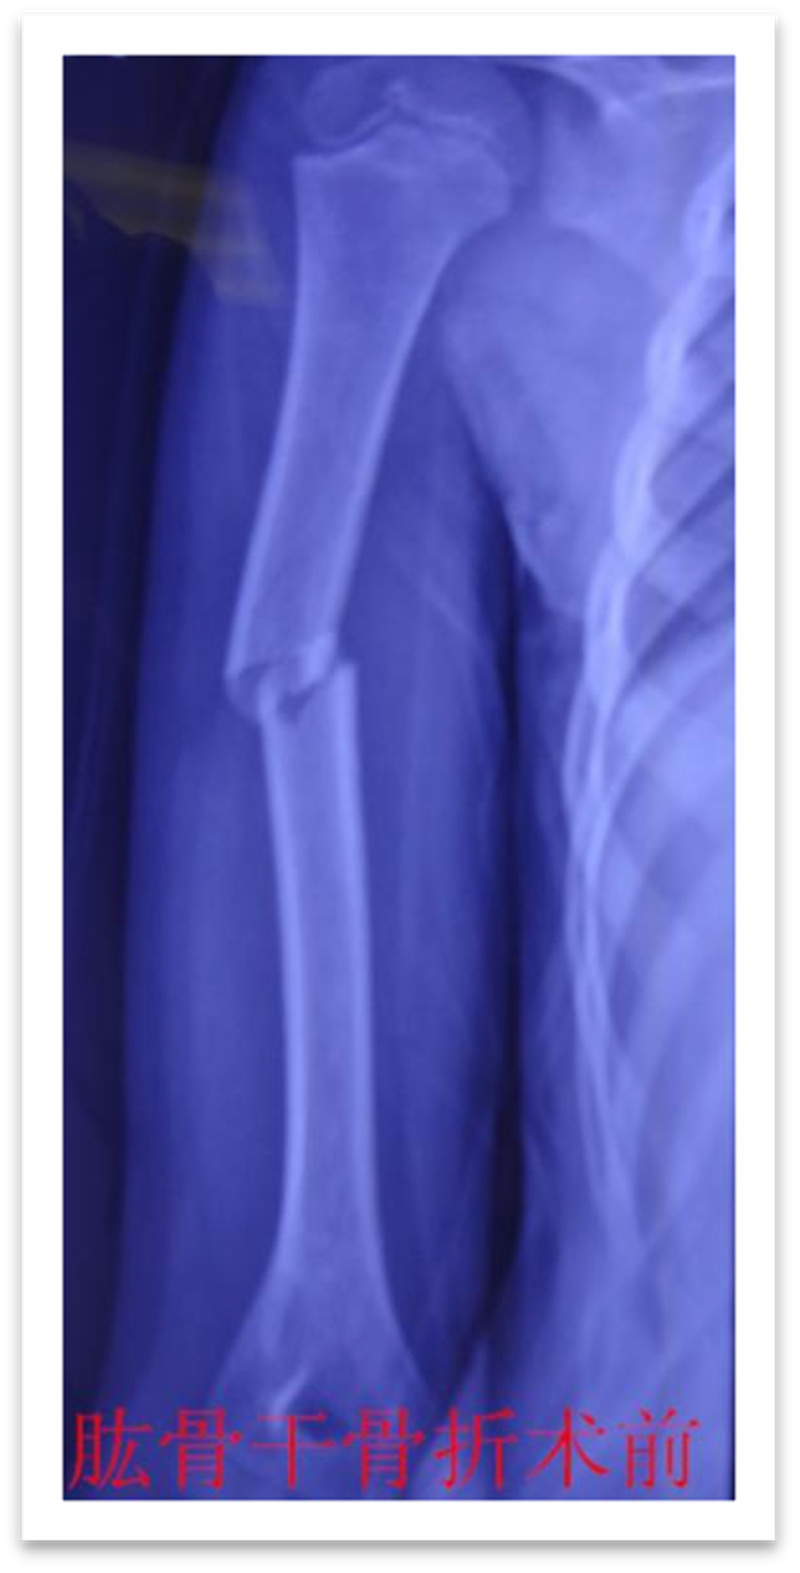

,弹性髓内钉内固定解决了这个矛盾。有人说,弹性髓内钉的出现是上天对儿童的恩惠。的确,弹性髓内钉是治疗小儿长管状骨骨骨折的一种理想、可靠的内固定方法。弹性髓内钉技术发源于法国,在欧洲广泛应用后,现已为全球所接受,被称为是儿童骨科界的一次革命。徐州儿童医院骨一科应用弹性髓内钉技术治疗四肢长管状骨骨折,具有创伤小、恢复快、并发症相对少,孩子能较快恢复正常生活、学习等优点。该技术先将骨折闭合复位,通过微小的切口将特制的弹性髓内钉置入骨髓腔,达到固定骨折的目的。适用于肱骨,股骨,尺桡骨等部位的常见骨折。